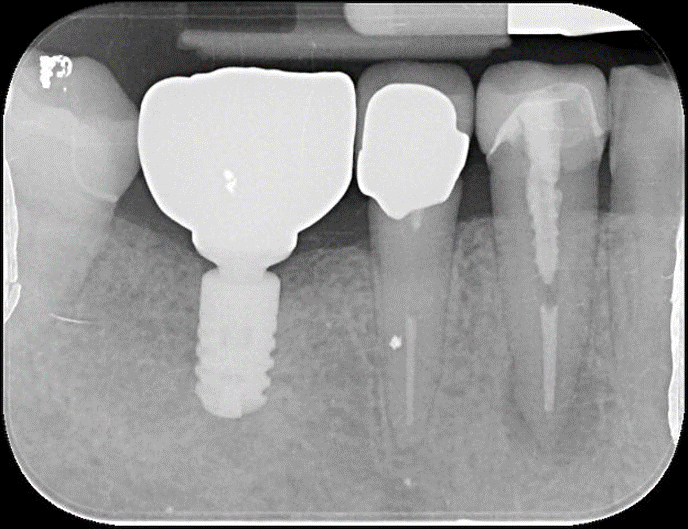

治療前,左下第一大臼齒嚴重蛀牙

治療前,蛀牙至牙根處